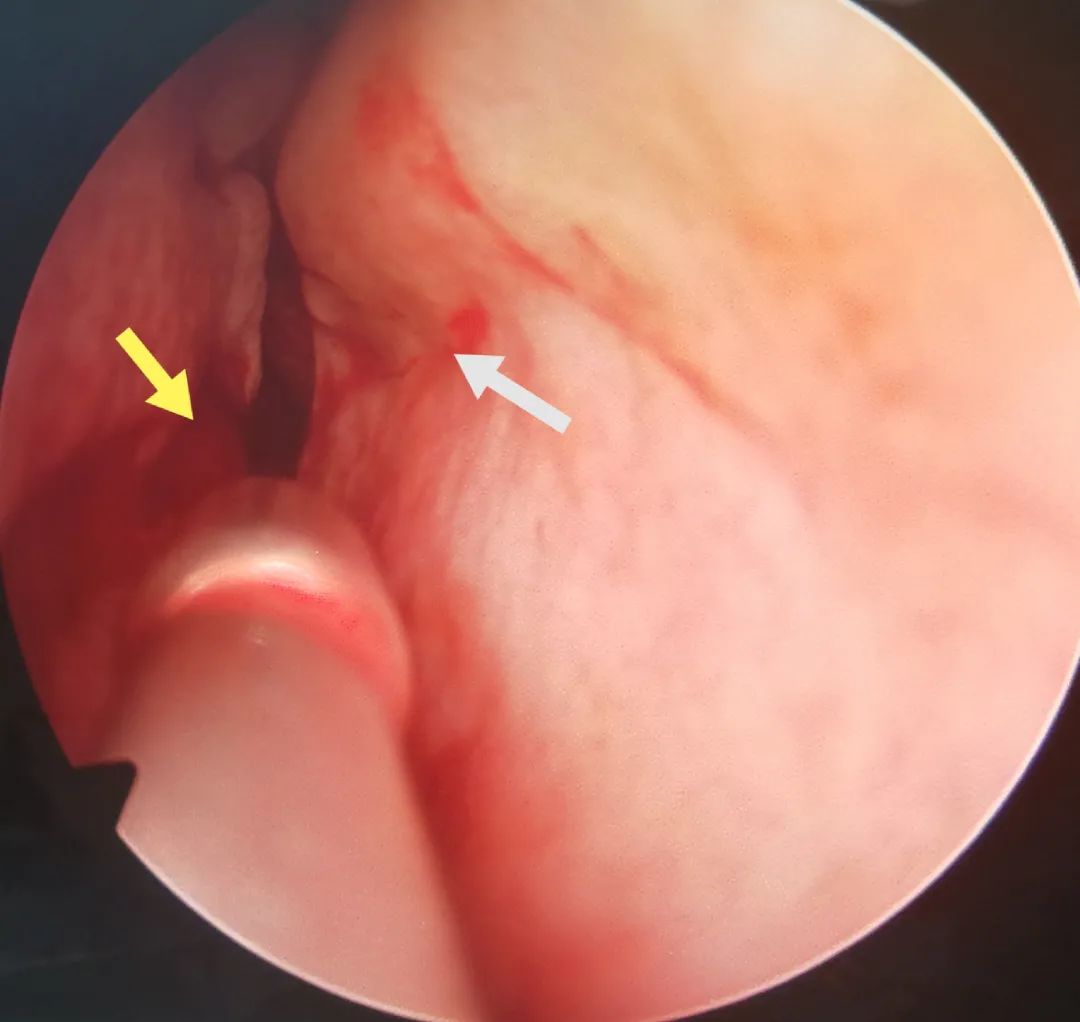

重点来了!手术价值解说:下面这几张图能够很好的说明了鼻中隔板块骨的错位、以及这种错位对鼻甲功能的损伤和限制 。 也印证了“鼻中隔偏曲矫正”手术的价值和必要性 。

图1

图1.左侧鼻腔 。 蓝色箭头就是鼻中隔受到顶部压力后 , 板块相互挤压隆起而产生的骨刺 。 这个骨刺正好扎在左侧下鼻甲的“海绵体”上 , 对鼻甲血管的“舒缩”造成很大限制 , 形成“鼻周期紊乱” 。